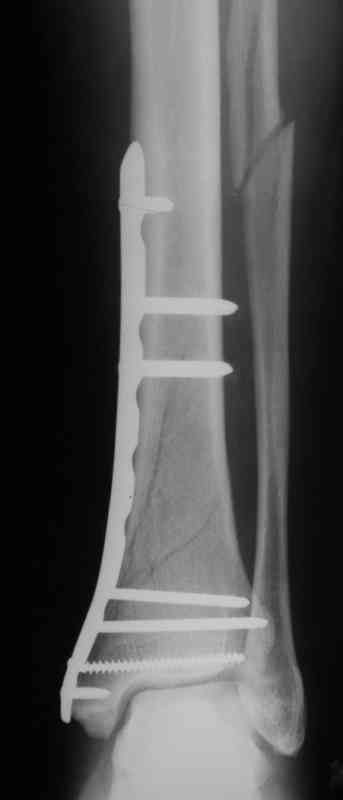

Выполнил MIPO предизогнутой метафизарной LCP

Красиво получилось, поздравляю. Насчет немедленной полной нагрузки, как на гвозде, про что Алексей Семенистый говорит - будете разрешать сразу?

Подход индивидуальный, учитывая массу больного около 130кг, разрешу частичную нагрузку 15-20кг, через 4нед. Rg-контроль, при отсутствии признаков нестабильности полная нагрузка

И все же немного критики:1) Вы добивались анатомичной репозиции, которая требует абсолютной стабильности, которая в свою очередь возможноа только в условиях межфрагментарной компрессии. Пластина уложена как мостовидная, не хватает стягивающнго винта. 2) есть укорочение малоберцовой кости, необхордимо восстановить ее длину! В таком виде я бы не стал разрешать раннюю нагрузку. Добавить самую малость: стягивающий винт и остеосинтез малоберцовой кости и больной может наступать сразу.

В этом случае остеосинтез выполнялся малоинвазивно и я не добивался абсолютной стабильности преднамеренно. Стабильность относительная и ст. её зависит от механических свойств импланта;возможно, нужно было взять длиннее пластину, увеличив её рабочую длину